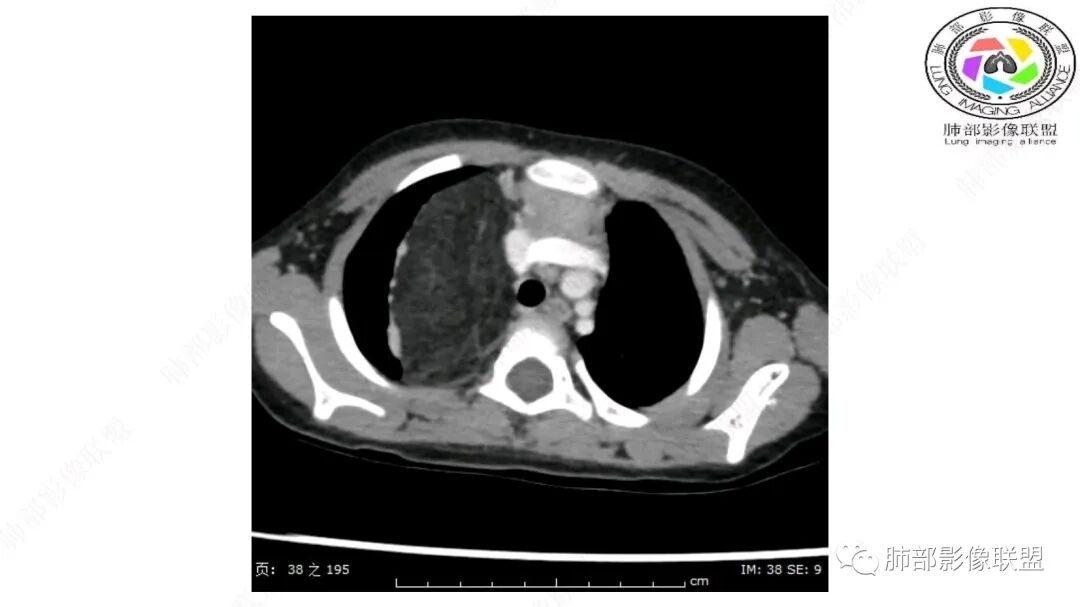

第一个问题:定位:肺内?纵隔?

病灶属于交界区,主体位于肺内,占位效应明显,前方突入胸壁,胸腺受压变形,胸膜显示欠清楚;病灶包绕上叶肺动脉;似乎有体动脉供血。符合肺内的点:包绕上叶肺动脉分支;符合纵隔的点:前方似乎突入胸壁,与胸腺关系比较密切,但是与上腔静脉的关系提示病灶不支持纵隔来源,前纵隔的常规会将上腔静脉受压后移、外移,这是不符合的。

从这个角度符合肺内的,有一点不太踏实的是:似乎突入前胸壁。

2.肺动脉穿行也许是肺内来源最重要支持点!